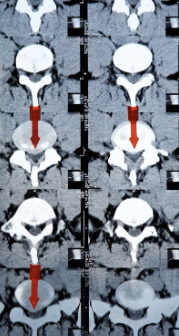

허리디스크는 디스크가 터져서 신경을 누를 경우 생기는 것으로 보통 4,5번에서 많이 발생하고 디스크가 터진 양이 적다면 터진 순간부터 수분이 날아가면서 양이 많이 없어지는데 그렇지 않고 양이 많을 경우 극심한 통증이 생깁니다.

허리디스크를 정확하게 진단하기 위해서는 엑스레이로는 힘들며, MRI를 통해 검사해야 정확하게 볼 수 있습니다.